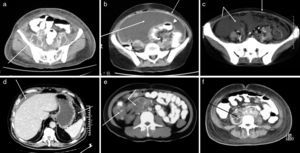

High-resolution computed axial tomography scan (CAT scan)A high-resolution CAT scan was performed in 12 patients with TB, six men and six women, three with VIH-infection and three with chronic malnutrition. The presence of ascites was proven in the 12 (100%) cases. In 10 cases (83%), a thickening of the intestinal loop wall, blindgut and omentum was observed, and in seven cases (58%), an increase of the peripheral fat density was observed. In six cases (50%), a significant increase of the size of the lymphatic, abdominal and retroperitoneal nodes was identified, with small mesenteric nodules, some of them calcified. Pulmonary involvement was found in 66%, pleural involvement in 50%, and pericardial involvement in 16% (Fig. 1, Table 3).

(a) Adenomegaly at the common iliac chains with hypodense nodes and hyperdense wall. (b) Thickening of the peritoneum, abundant ascites, thickening of the intestinal loop wall and evident lymphatic nodes. (c) Diffuse increase in the attenuation of the peritoneal fat. Calcified mesenteric lymph nodes of granulomatous aspect. (d) Ascites of perihepatic distribution, discreet increase of peripheral fat density and small nodules. (e) Important thickening of the blindgut wall, hypodense lymph nodes. Increased density in the mesenteric fat. (f) Wide hypodense retroperitoneal adenomegaly with well-defined precaval and paraaortic walls adjacent to the caeliac artery and portal hepatic region.